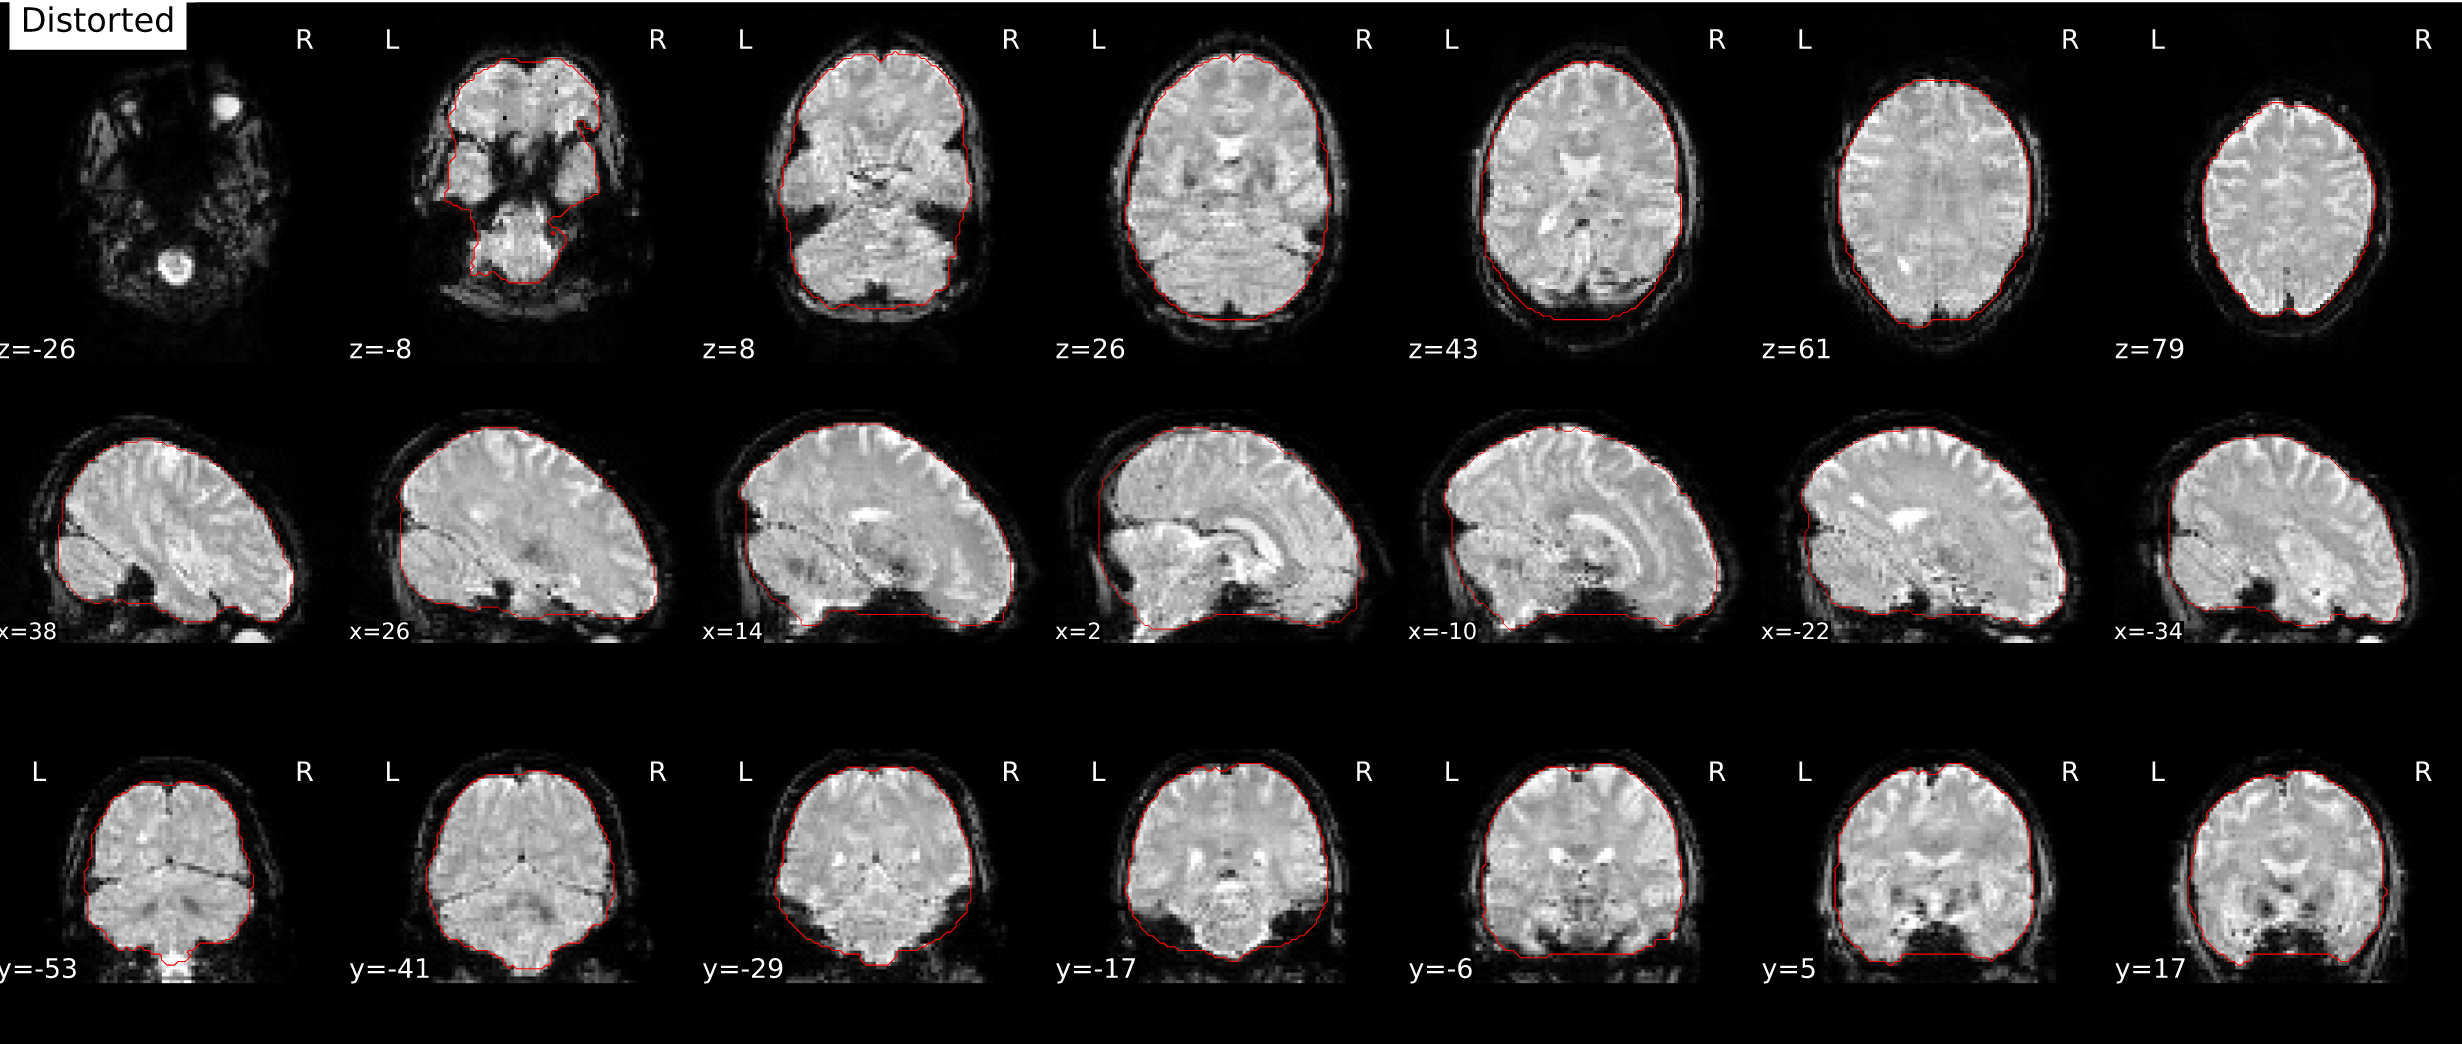

Allows SimpleBeforeAfter reports to rotate images with respect to the cardinal axes. This is motivated in the context of SDC correction, to give a clearer look at the distortions.

Screen Shot 2021-08-31 at 3 43 06 PM

Screen Shot 2021-08-31 at 3 43 15 PM